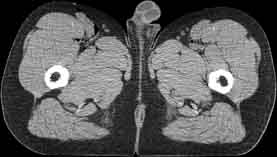

Visible Human male: Sectio transversalis 1958

CT